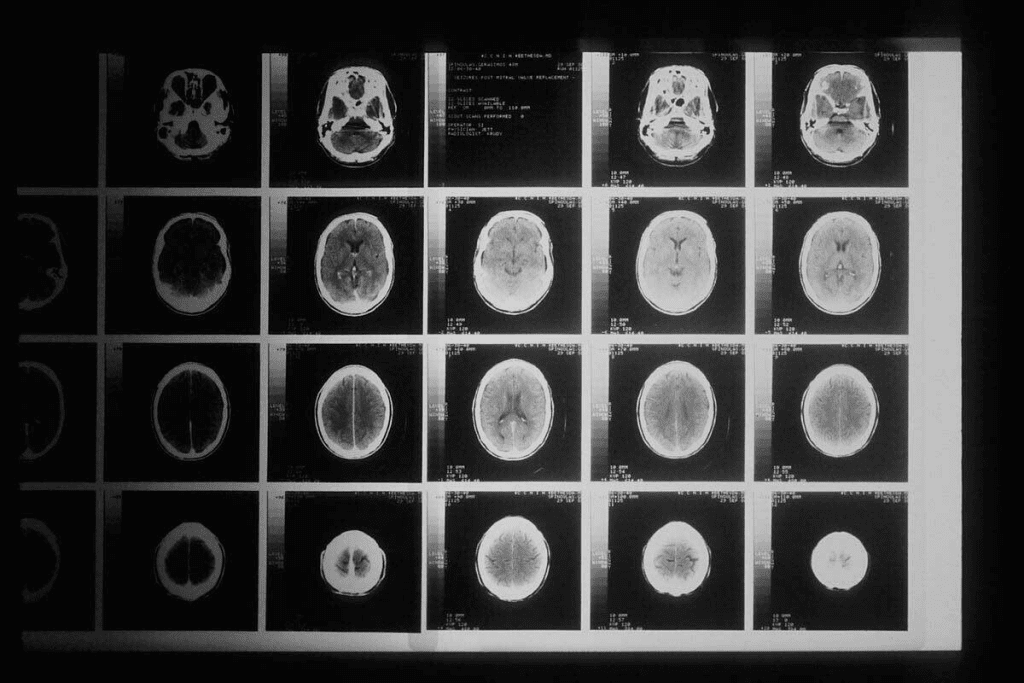

Understanding MRI Modalities in Brain Tumor Imaging

Knowing about MRI modalities is key for spotting brain tumors right and planning treatments well. MRI shows grayscale images that show different tissue types. These include proton density, FLAIR, T1-weighted, and T2-weighted images. They help doctors understand tumors and make decisions.

T1-Weighted vs. T2-Weighted Sequences

T1-weighted and T2-weighted sequences are basic in brain tumor scans. T1-weighted images show body parts clearly, and they’re better after contrast. This shows where the contrast goes, marking tumor edges. On the other hand, T2-weighted images spot water changes well, helping find swelling and lesions.

Knowing the difference between T1 and T2 images is important. Tumors look darker on T1 and brighter on T2. This helps see how big a tumor is, where it is, and if it’s spreading.

FLAIR and Contrast-Enhanced Protocols

FLAIR and contrast-enhanced scans add more to MRI’s power in brain tumor imaging. FLAIR sequences help see lesions near CSF spaces better. This is great for spotting swelling around tumors and telling it apart from fluid.

Contrast-enhanced MRI uses gadolinium to show where the blood-brain barrier is broken. This is common in brain tumors. It’s key for seeing tumor edges and how well treatments are working.